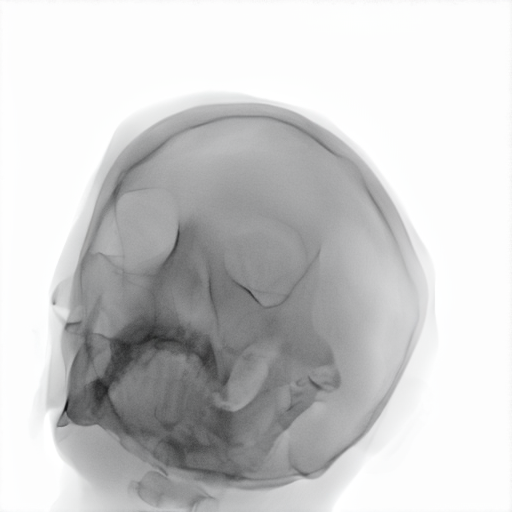

Refer to caption

Figure 3: Trade-off between structural fidelity (SSIM) and realism (CFID) for the evaluated models.

As shown in Table 3, CycleGAN-Turbo achieves the strongest performance on distributional metrics such as CFID and density, but this comes at the cost of anatomical fidelity. The implementation of the structural similarity loss did not yield the expected outcomes. The qualitative results in Table 2 reveal that it introduces spurious features, especially in the second row, undermining structural correctness. In contrast, Hierarchy Flow preserves anatomical details exceptionally well by applying minimal transformation, resulting in outputs that closely resemble the input and thus offer limited to no domain adaptation. As noted in Figure 3 and Table 3, the model completely breaks down at high style strengths values without improvement in FID.

MedShift is evaluated in three τ\tau settings to explore the trade-off between structural preservation and generative realism. At τ=0.6\tau=0.6, the model is second only to HierarchyFlow in maintaining structure, while significantly outperforming it in CFID and coverage. The low-fidelity setting (τ=0.3\tau=0.3) reaches CFID values comparable to CycleGAN but with far fewer anatomical distortions. The intermediate configuration (τ=0.45\tau=0.45) provides a good trade-off, as seen in Table 2. Z-STAR maintains structure but fails to transfer style effectively to the lower jaw, while SDEdit captures pixel intensities well but introduces artifacts into the cranial region, particularly in the second example. As shown in Figure 3, MedShift achieves a more favorable balance between structural fidelity and image realism across all τ\tau settings, outperforming the other models in this trade-off space. This reinforces the findings based on average ranking, confirming MedShift as the most well-rounded strategy.